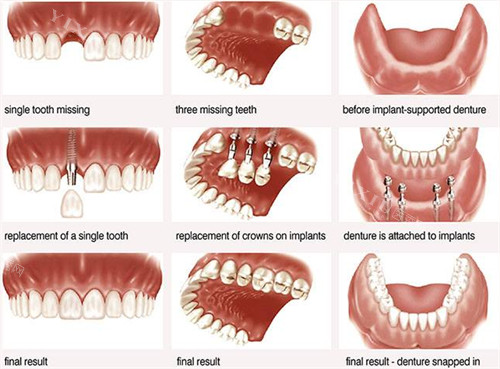

雅伦美口腔棠德西路院区在种植牙领域具有显著优势,其采用的种植系统涵盖多个国内外老牌品牌,能够满足不同患者的个性化需求。目前院区提供的种植体选择包括:美国皓圣种植系统(价格区间5250元起/颗)、德国ICX种植系统(5800元起/颗)、瑞士ITI种植系统(12800元起/颗)以及瑞典诺贝尔种植系统(12000元起/颗)。

每种系统都有其独特的技术特点和适应症,经验充足的种植医生会根据患者骨质条件、咬合关系及预算等因素,推荐适合的种植方案。

该院区的种植牙质保政策在广州口腔医疗行业中处于比较靠前水平。根据种植体品牌和治疗方案的不同,提供5年至长期不等的质保服务。质保范围通常包括种植体本身的机械故障、 osseointegration(骨结合)失败等情况。值得注意的是,雅伦美口腔的质保并非简单的"一刀切",而是建立了完善的三维评估体系,通过术前CBCT检查、术中导航和术后定期回访,确保每个环节都达到理想标准,从而为质保约定提供科学依据。

针对半口或全口缺牙患者,院区推出了高性价比的套餐服务:半口种植牙套餐30000元起,全口种植牙套餐50000元起。这些套餐不仅包含种植体和修复体费用,还涵盖了必要的检查、影像学评估和术后随访服务,让患者能够清晰了解总体治疗成本,避免隐性消费。